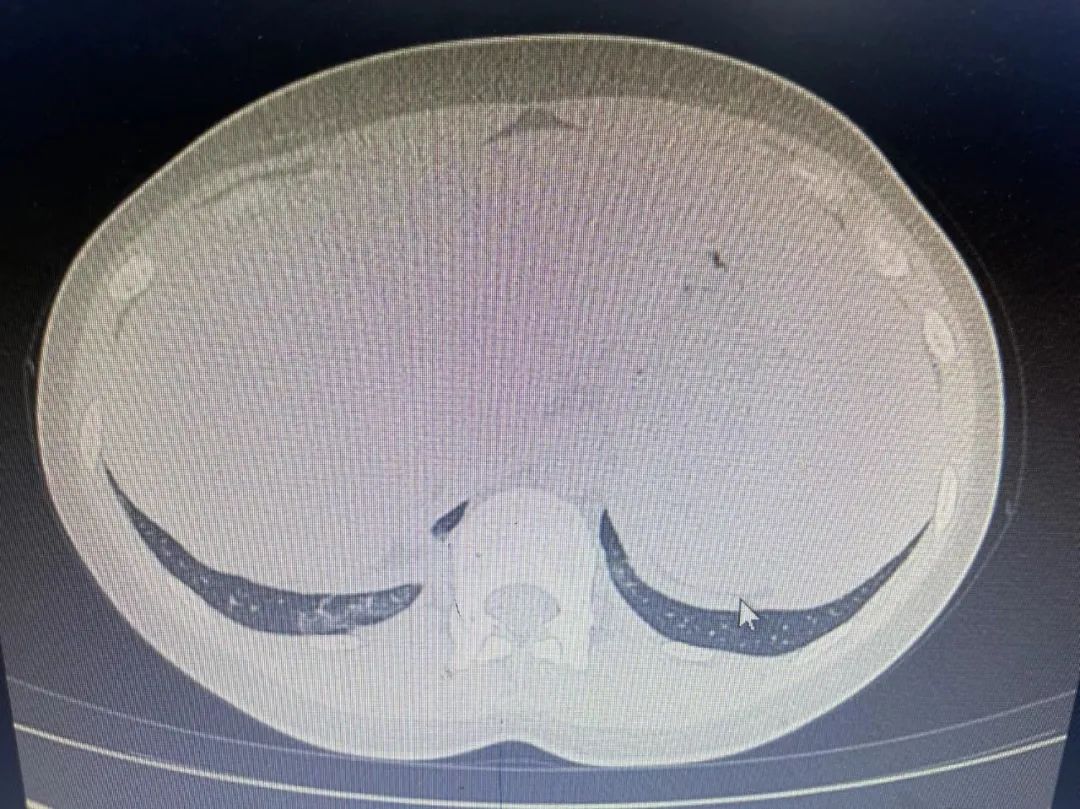

1日前就诊于我院发热门诊,胸部CT:左肺下叶局限性小斑片影,少许炎症可能。血常规(11-22):大致正常。CRP(11-22):67.27mg/l。口服“头孢”抗生素治疗1次(具体不详)。

胸部CT